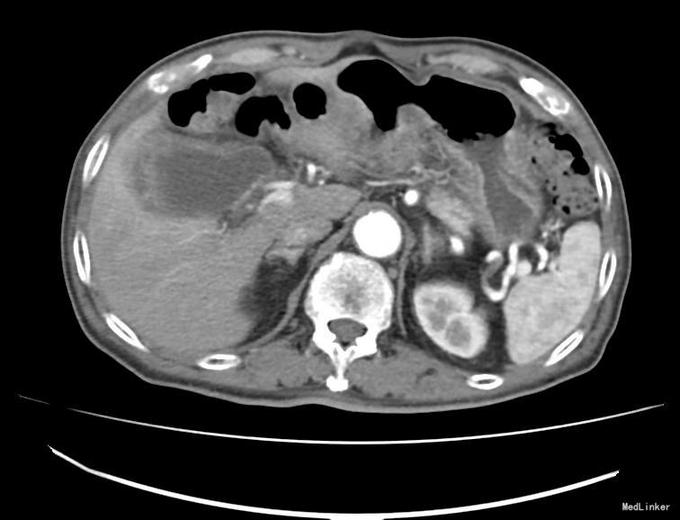

查体:右上腹轻压痛,无反跳痛、肌紧张。墨菲氏征弱阳性。 辅助检查:腹部CT:胆囊体积增大,壁增厚,以胆囊底部为著,增强扫描可见轻度强化,胆囊周围可见积液。MRI:胆囊增大,壁增厚,壁内可见多发结节状低信号灶。胆囊内可见泥沙样短T2信号影。